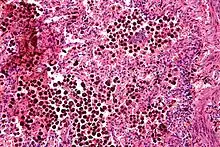

Some medical conditions can also make patients susceptible to bleeding. These are conditions that affect the normal hemostatic (bleeding-control) functions of the body. Such conditions either are, or cause, bleeding diatheses. Hemostasis involves several components. The main components of the hemostatic system include platelets and the coagulation system.

Platelets are small blood components that form a plug in the blood vessel wall that stops bleeding. Platelets also produce a variety of substances that stimulate the production of a blood clot. One of the most common causes of increased bleeding risk is exposure to nonsteroidal anti-inflammatory drugs (NSAIDs). The prototype for these drugs is aspirin, which inhibits the production of thromboxane. NSAIDs inhibit the activation of platelets, and thereby increase the risk of bleeding. The effect of aspirin is irreversible; therefore, the inhibitory effect of aspirin is present until the platelets have been replaced (about ten days). Other NSAIDs, such as "ibuprofen" (Motrin) and related drugs, are reversible and therefore, the effect on platelets is not as long-lived.

There are several named coagulation factors that interact in a complex way to form blood clots, as discussed in the article on coagulation. Deficiencies of coagulation factors are associated with clinical bleeding. For instance, deficiency of Factor VIII causes classic hemophilia A while deficiencies of Factor IX cause "Christmas disease"(hemophilia B). Antibodies to Factor VIII can also inactivate the Factor VII and precipitate bleeding that is very difficult to control. This is a rare condition that is most likely to occur in older patients and in those with autoimmune diseases. Another common bleeding disorder is Von Willebrand disease. It is caused by a deficiency or abnormal function of the "Von Willebrand" factor, which is involved in platelet activation. Deficiencies in other factors, such as factor XIII or factor VII are occasionally seen, but may not be associated with severe bleeding and are not as commonly diagnosed.